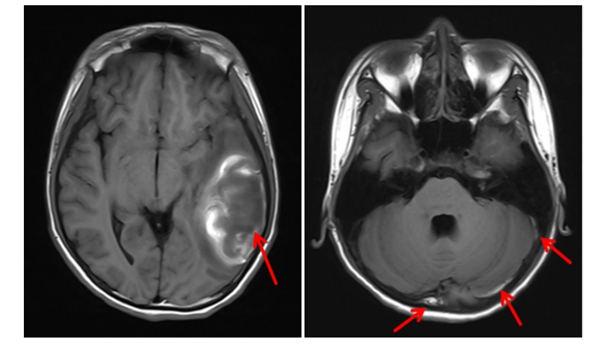

近日,中山大学附属第一医院(简称中山一院)广西医院放射影像科与儿科团队通力合作,通过联合会诊和精准的影像学分析,完成一例疑难病例的精准诊断,找出患者病因,并制定了科学合理的治疗方案。目前,患者已得到针对性治疗,病情稳定向好。12岁的小卓(化名)因持续呕吐、腹痛伴发热在当地卫生院接受“急性肠胃炎”对症治疗,但始终未见好转,最终来到皇冠足球投注网 儿科就诊。在皇冠足球投注网 住院期间,儿科主任黄雪琼在查房过...